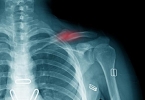

• 骨质疏松性骨折有什么特点

骨质疏松性骨折有什么特点

骨质疏松性骨折通常具有疼痛、畸形、活动受限等特点,多见于脊柱、髋部、腕部等部位。骨质疏松性骨折主要由骨量减少、骨微结构破坏导致骨脆性增加引起,常见于绝经后女性和老年人群。骨质疏松性骨折的疼痛特点为局部 ...